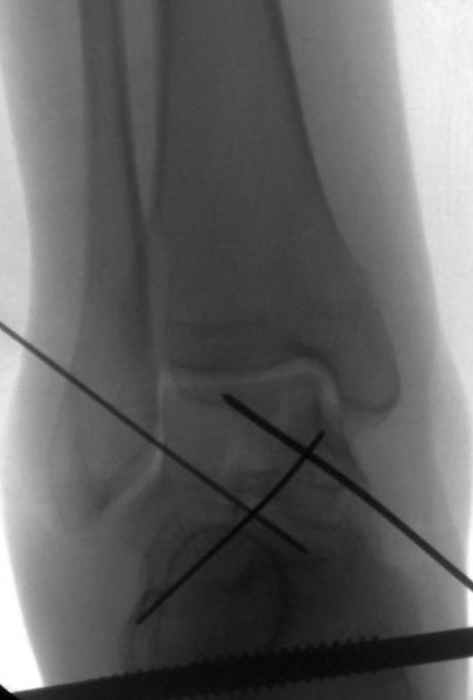

Вдогонку по поводу перелома таранной кости, больная 81, не страдает диабетом, перелом закрытый, в первый же день поступления ограничились временным наружным фиксатором (как на снимке).

Планировалась открытая фиксация после спадения отека, но больная пожелала лечиться по месту жительству в другом штате..

За пару недель насчитал 5 больных с переломом таранной кости, из них двое с двусторонним повреждением.

Из-за отека на стопе тактика лечения у всех была

одинаковая: временная наружная фиксация до спадения отека, при изолированных переломах они выписывались домой и через дней 7 госпитализировались на оперативное лечение.

Примеры на снимке...